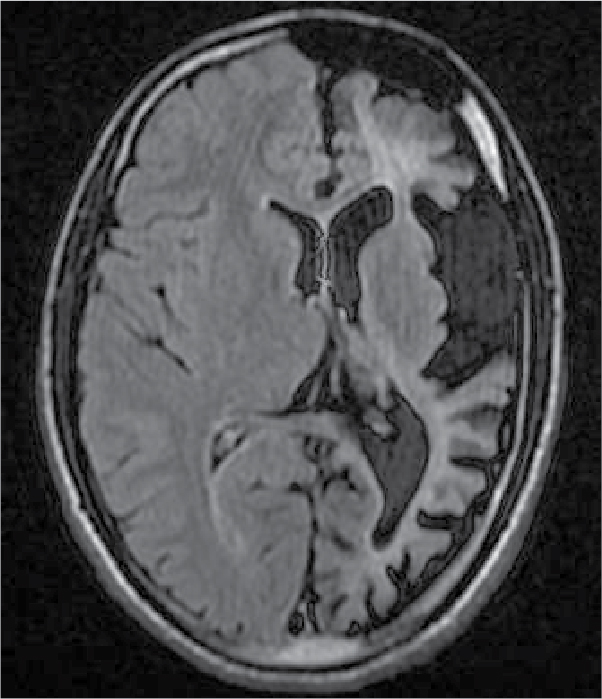

On examination, patient was conscious and oriented to time, place and person. There was extension at right elbow joint; pronated forearm and flexion at wrist joint (Fig. 1). Mental status examination revealed impaired calculation and Mini-Mental State Examination (MMSE) revealed a score of 24/30. On cranial nerve examination, patient had right upper motor neuron (UMN) type of facial nerve palsy. On motor examination, patient had gross wasting in right upper and lower limbs. Tone was markedly increased on right side of body with reduced power (3/5), brisk deep tendon reflexes and reduced sensation to touch, pain, temperature, vibration and proprioception. Plantar response was extensor on right side. Biochemistry was unremarkable. A provisional diagnosis of insidious onset gradually progressive sensorimotor hemiparesis with focal to generalized epilepsy with mental retardation was made. Noncontrast computed tomography (NCCT) head and magnetic resonance imaging (MRI) brain was performed, which revealed left cerebral hemiatrophy as evidenced by reduction in volume, prominence of cerebral sulci and dilation of left lateral ventricle. No other bony vault abnormality or prominence of frontal and mastoid air cells were seen (Figs. 2-4). Electroencephalogram (EEG) revealed epileptiform discharges in the form of sharp and slow wave complexes. Histopathology could not be done as attendants were not willing. Patient fulfilled the diagnostic criteria of RE (Table 1). He was treated with tablet phenytoin 100 mg TDS; tablet azathioprine 50 mg OD was started to halt progression of the disease. Patient had no episode of seizure thereafter. He was advised follow-up and repeat MRI brain was planned to check for any progression.

Figure 3. FLAIR transverse section showing loss of volume of white matter in left cerebral hemisphere with thinning of gyri and ex vacuo dilatation of left lateral ventricle.